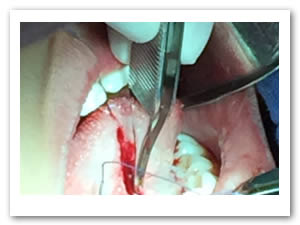

• Se pasa una sutura sin anudar en la punta de la lengua para traccionar la misma y facilitar las maniobras quirúrgicas. Posteriormente se utilizan dos pinzas de mosco, una curva y una recta pinzando el frenillo en su borde superior e inferior para limitar sus bordes. Figuras 3 y 4.

Figura 3. Sutura sin anudar en punta de la lengua

Figura 4. Pinzado del frenillo